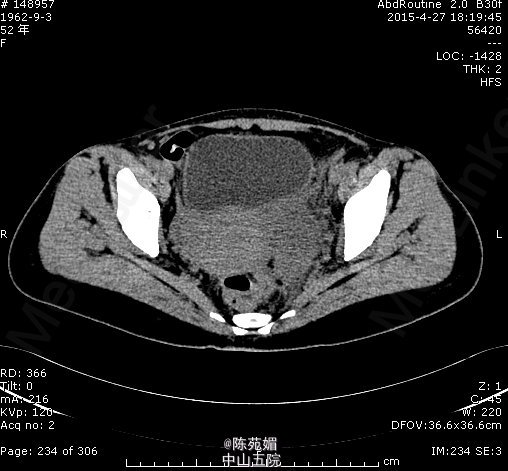

入院诊断:1.腹痛、发热查因:急性肠胃炎?2.地中海贫血3.脾切除术后。入院后我院腹部CT示:左附件区混杂密度肿块,建议进一步检查。血常规示:WBC 19.05×10^9/L,HB 88g/L,余肝肾功能未见明显异常。请妇科会诊,考虑左附件脓肿形成可能性大,遂转妇科进一步治疗。感染控制后,行腹腔镜下左附件切除术。术中见左侧附件肿大,被乙状结肠和直肠包裹,分离粘连后见左侧输卵管卵巢膨大、水肿,破裂后流出黄白色脓液,切除左侧卵巢、输卵管。术后病理示:符合脓肿组织学图像。